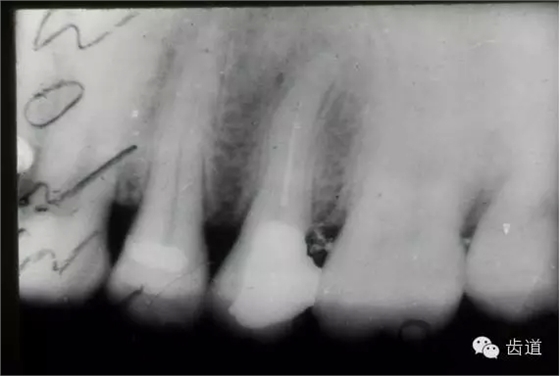

(3)髓室底穿孔:處理方法同上。同時(shí)找到根管口,按常規(guī)進(jìn)行根管預(yù)備和充填。如穿孔范圍太大易導(dǎo)致根分歧病變,予后欠佳??尚懈芡饪啤?/span> (4)根管壁形成臺(tái)階:先換小號(hào)銼去除臺(tái)階,再順序擴(kuò)挫。如根管壁穿孔,找到主根管進(jìn)行預(yù)備后,主根管及側(cè)穿道同時(shí)充填。在根尖1/3或根尖彎曲處側(cè)穿,根充后,配合根尖手術(shù)——根切+倒充填。 (三)髓腔壁穿孔的預(yù)防 1.掌握每個(gè)牙齒的髓腔解剖形態(tài)及其在牙齒表面的投影范圍。 2.術(shù)前拍X線片。 3.進(jìn)行規(guī)范化操作,隨時(shí)與X線片核對(duì)器械進(jìn)入方向及進(jìn)入深度。 器械折斷在根管內(nèi),阻塞根管,妨礙治療操作。如不能取出,使根管治療不能繼續(xù)進(jìn)行,不得不輔以根尖手術(shù)。 左上7近中頰根器械折斷 右上6腭根器械折斷 1.器械本身的原因 材料質(zhì)量欠佳,受力后易折斷。 器械反復(fù)使用,產(chǎn)生折痕,用力后也易折斷。 消毒方法不當(dāng),消毒液中未放防銹劑,器械銹蝕易折。 2.術(shù)者器械使用不當(dāng) 遇有阻力,仍強(qiáng)行進(jìn)入,用力過(guò)大過(guò)猛,超過(guò)了器械所能承受的程度 未按操作要求使用器械(跳號(hào)) 器械在細(xì)窄根管內(nèi)被卡住后,仍勉強(qiáng)旋轉(zhuǎn)器械柄 折斷于根管內(nèi)的器械要盡量取出,若無(wú)法取出經(jīng)常規(guī)充填后,成功率不受明顯影響。 1.折斷器械有一部分露在根管口外,用鑷子或持針器夾取出。 2.器械斷端在根管口內(nèi):用超聲根管銼在該器械旁增隙,通過(guò)超聲震蕩和沖洗,可將折斷器械從根管內(nèi)震動(dòng)沖出。在手術(shù)顯微鏡下直視操作,大大提高了取出的成功率。 3.折斷器械尖端已超出根尖孔:無(wú)癥狀不處理;有疼痛則作根尖手術(shù)取出。 4.折斷器械較長(zhǎng),各種方法均不能取出,可作根管電解消毒,塑化治療或塑化劑處理,根管充填。 若患牙根尖有病變,必要時(shí)作根尖切除+倒充填。 1.使用前認(rèn)真檢查器械有無(wú)生銹、折痕、螺紋松解等現(xiàn)象。 2.嚴(yán)格按器械使用規(guī)則進(jìn)行操作。 3.使用機(jī)用根管器械,應(yīng)支點(diǎn)穩(wěn)、轉(zhuǎn)速慢,并只能應(yīng)用于直的根管。 4.制備開(kāi)髓洞形時(shí),應(yīng)充分暴露根管口,對(duì)彎曲根管能盡量減少其彎曲度,對(duì)彎曲度在30o以上的根管盡量采用超聲根管預(yù)備并使用鎳鈦根管挫。 5.控制器械使用次數(shù):根管銼刃部的鋒利程度隨所預(yù)備的根管數(shù)目增加而降低。 25#以下器械只能用1—2次,30#—50#器械可用二次。 牙折分為冠折、根折及冠根折三種。根管治療后,由于牙折導(dǎo)致拔除者屢見(jiàn),故應(yīng)引起足夠重視。 (一)牙折發(fā)生原因 1.經(jīng)根管治療的牙齒,因失去了牙髓的營(yíng)養(yǎng)而脆性增大。 2.制備開(kāi)髓洞形時(shí),過(guò)多的磨除了牙體組織,削弱了牙體組織強(qiáng)度。 3.根管清理和成形以及做冠樁預(yù)備過(guò)程中,過(guò)多的磨除根管壁,削弱了牙根強(qiáng)度。 4.用牙膠做根管充填時(shí),側(cè)向或垂直壓力過(guò)大,均可造成牙根縱折。 5.其他:根管釘、樁的采用;熱塑冷凝的牙膠尖填入根管后自身體積膨脹;牙周受累的牙齒,支持骨喪失,也增加了牙折的機(jī)會(huì)。 (二)牙折的處理 應(yīng)盡可能保存患牙 1.冠折:根據(jù)折斷的牙體組織的多少及部位,可分別選擇充填;加螺旋釘固位;全冠或樁冠修復(fù)。 2.冠根折:折斷線在齦下不足3mm,配合齦切術(shù)或冠延長(zhǎng)術(shù),將斷端暴露在齦上,然后根據(jù)缺損情況考慮冠修復(fù)的種類。 折斷線在齦下超過(guò)3mm,患牙牙根較長(zhǎng),正畸力將牙根牽引,無(wú)條件做正畸治療的單根牙則拔除,多根牙則可做截根或半切除術(shù)。 3.根橫折:在冠方1/3處理方法同冠根折。 在根中1/3根折線不與牙周袋相通,做根內(nèi)固定,加牙冠部夾板固定4—8周。在根尖1/3,調(diào)合 解除創(chuàng)傷力,如有癥狀做根尖切除術(shù)。 4.根縱折:?jiǎn)胃绖t拔除;多根牙做截根術(shù)或半切除術(shù)。也有報(bào)告,用切開(kāi)翻瓣暴露縱折牙根,粘接劑粘合裂根的方法保留縱折牙牙根,若以后出現(xiàn)牙周袋則拔除。 (三)牙折的預(yù)防 1.根管治療過(guò)程中,有薄壁銳尖或陡峭的無(wú)基釉質(zhì),應(yīng)及時(shí)降低咬合或磨除。根管治療后,常規(guī)調(diào)合。 2.根管治療應(yīng)遵循:在保證治療的前提下,盡量保留健康的牙體組織。 3.根管充填操作用力適度。 五、下唇麻木 (一)發(fā)生原因:主要由下齒槽神經(jīng)損傷所致 1.治療操作中藥物、器械或根充物超出根尖孔,進(jìn)入下頜管損傷下齒槽神經(jīng) 2.解剖因素:下頜牙齒根尖距下頜管太近,有些牙根與下頜管相連,以下頜第二恒磨牙多見(jiàn) 左下7根充后下唇麻木 左下5根管預(yù)備后下唇麻木 (二)處理: 1.根據(jù)病史認(rèn)真查找原因,如為炎癥刺激所致,應(yīng)積極治療根尖周炎,加口服營(yíng)養(yǎng)神經(jīng)藥物。 2.理化刺激所致,口服營(yíng)養(yǎng)神經(jīng)藥物。 (三)預(yù)防: 1.作根管治療前拍X線片,下頜牙齒應(yīng)特別注意與下頜管的關(guān)系。 2.準(zhǔn)確測(cè)量根管工作長(zhǎng)度,各種操作均在工作長(zhǎng)度范圍內(nèi)進(jìn)行。根管封藥不可過(guò)飽和,防止藥液溢出根尖孔。 此種意外發(fā)生,給患者帶來(lái)很大的精神壓力,如器械落入呼吸道,則增加更大的痛苦,應(yīng)慎重處理。 (一)發(fā)生原因 1.術(shù)者精神不集中 2.患者過(guò)于緊張不合作 3.患者體位不正確 4.器械從手中滑脫 (二)處理 1.醫(yī)護(hù)人員應(yīng)鎮(zhèn)靜,安撫患者。 2.立即拍腹部平片。 3.落入消化道應(yīng)住院觀察。 4.服用長(zhǎng)纖維及有潤(rùn)滑作用的食物,勿服瀉藥。 5.適當(dāng)走動(dòng),勿劇烈運(yùn)動(dòng)。 6.每天拍腹部X線片,檢查大便至排出。 7.落入呼吸道,應(yīng)請(qǐng)耳鼻喉科或胸外科醫(yī)生協(xié)助取出。 (三)預(yù)防: 1.針對(duì)原因預(yù)防。 2.治療時(shí)上橡皮障。 3.無(wú)條件用橡皮障,可在器械柄拴安全鏈。 皮下氣腫是根管治療中少見(jiàn)的并發(fā)癥 (一)臨床表現(xiàn) 根據(jù)患牙的部位不同,可分別出現(xiàn)在頰部、頸部、和眶周等疏松軟組織迅速腫脹、充血,有捻發(fā)音。捻發(fā)音是組織氣腫的病理特征,以此和其他腫脹做鑒別。如空氣向頸部移動(dòng)可引起呼吸困難。 (二)發(fā)生原因 1.用壓縮空氣吹干根管時(shí)間過(guò)長(zhǎng)。 2.使用過(guò)氧化氫液沖洗根管,將藥液壓出根尖孔。 不可加壓??! (三)處理 一般不需特殊治療,給予抗生素預(yù)防感染 上頜竇曲霉病、上頜竇疼痛、上頜竇炎癥等。 根管治療的各種并發(fā)癥,絕大多數(shù)情況是由術(shù)者操作不規(guī)范所致。在根管治療過(guò)程中,術(shù)者應(yīng)嚴(yán)格按照規(guī)程進(jìn)行每一步操作,這些并發(fā)癥是完全可以避免的。